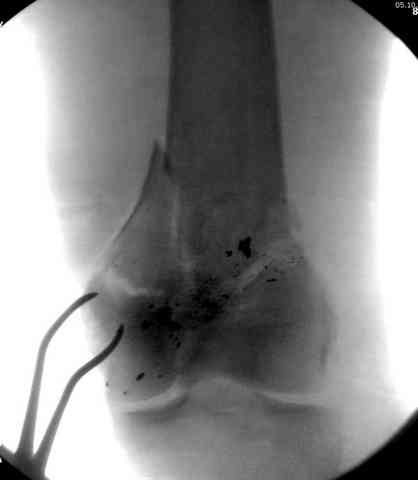

2 внутрисуставной перелом дистального бедра с удалением пули